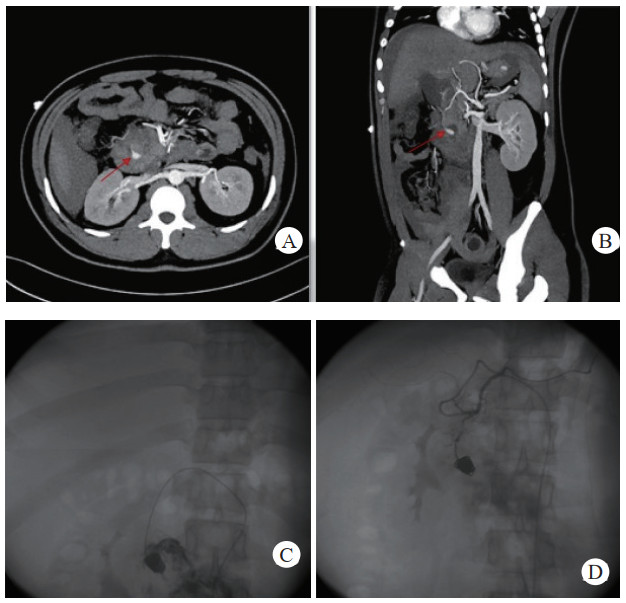

治疗后随诊复查CT显示,患者载瘤动脉及瘤腔内可见栓塞弹簧圈,血肿、假性动脉瘤瘤体体积明显缩小,未见血管再通与假性动脉瘤破裂,见图 2(病例2)。

| 注:图 2病例2 A为患者术前CT增强扫描,示胰腺炎影像,腹腔内见一血肿影,脾动脉起始段可见一瘤样扩张,内见对比剂填充;B、C分别为患者术后3 d及术后1个月复查CT增强示,血肿较前减小,原瘤样扩张处可见弹簧圈影及未见对比剂外溢 图 2 病例2术前、术后CT平扫及增强 |

患者经介入栓塞治疗后,长期的随访CT及增强CT中,未出现责任动脉或瘤体再次发生破裂导致二次出血、弹簧圈移位及血栓异位栓塞等并发症,见图 3(病例3)。

| 注:A、B为患者术前CT增强扫描及血管重建技术,示胰腺炎影像,腹腔内见一血肿影,内可见与动脉强化一致的动脉瘤影像(箭头示),其供血动脉为胃左动脉;C为患者术后三天复查CT增强扫描,示血肿较前吸收减小,内见弹簧圈影及未见对比剂外溢。D为患者术后三年复查CT增强示,血肿消失,原动脉瘤处可见弹簧圈影及未见对比剂外溢 图 3 病例3术前、术后CT平扫及增强 |